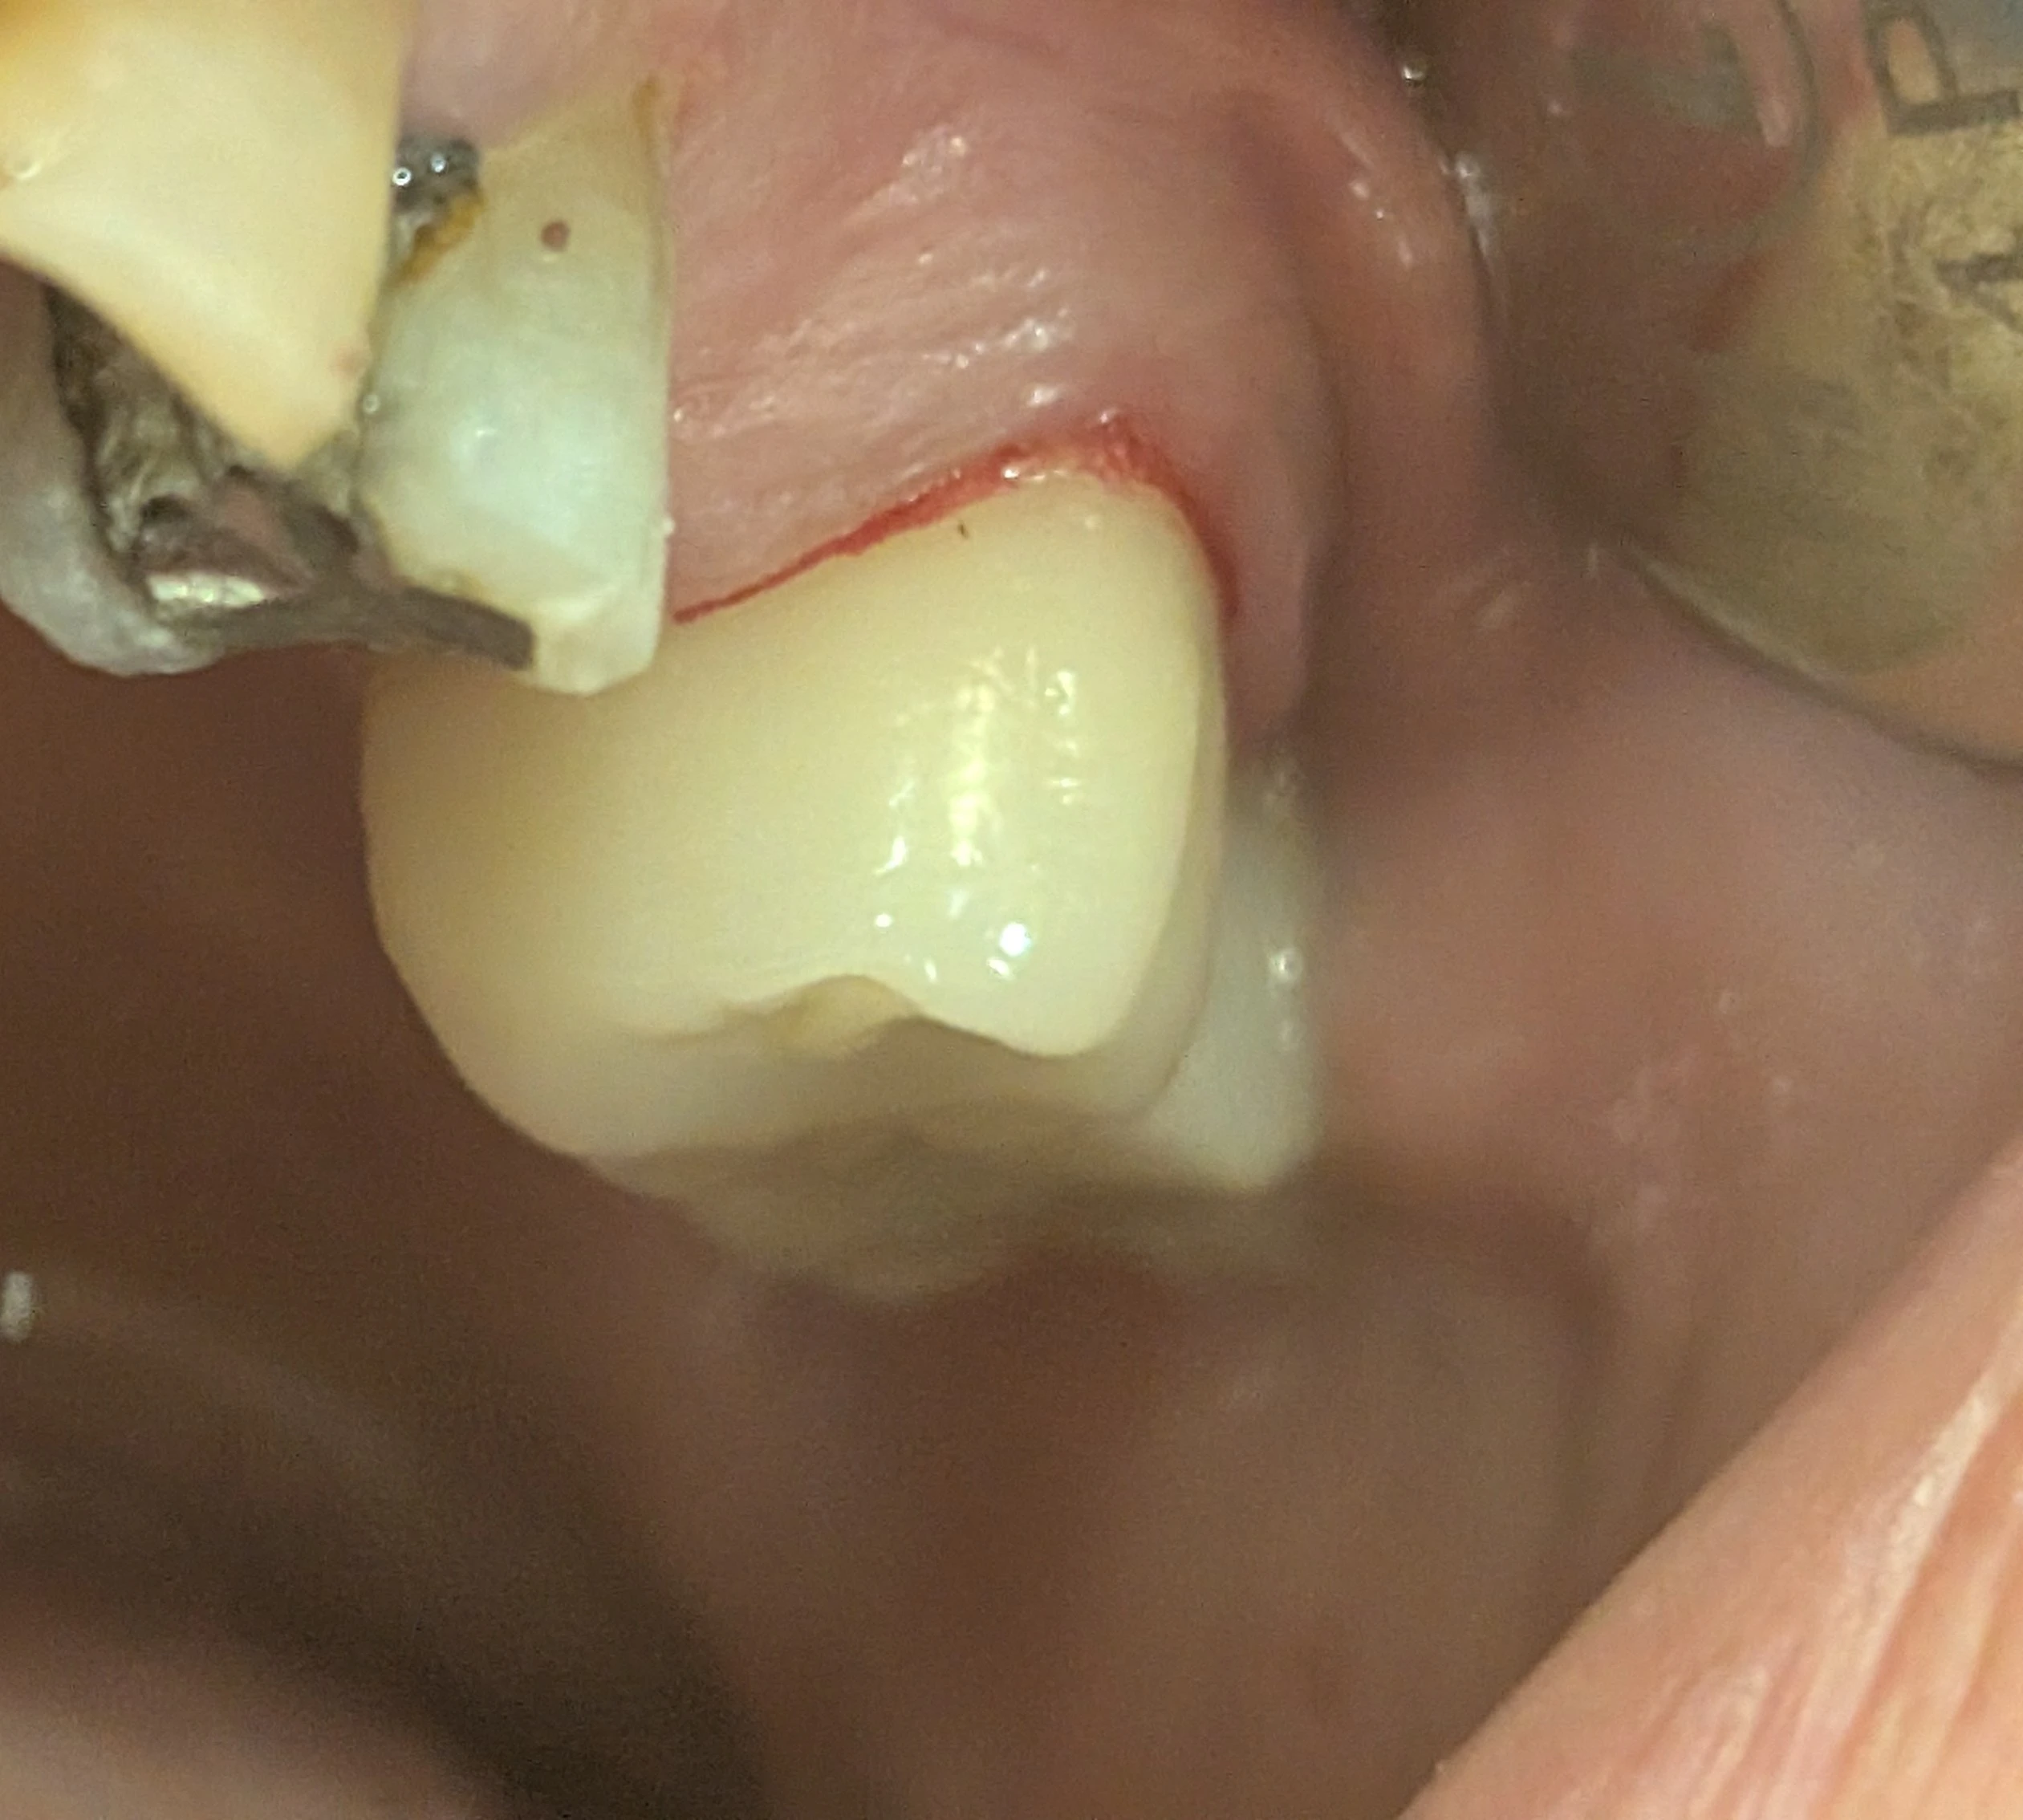

افزایش سطح قابل رؤیت تاج در فقدان دندان مزیالی می‌تواند ادراک اندازه را تغییر دهد.

در دندان‌های خلفی، در شرایط طبیعی بیمار عمدتاً سطح باکال دندان را می‌بیند. اما زمانی که دندان مزیالی از دست رفته باشد، سطح مزیال تاج نیز وارد میدان دید می‌شود.

در این وضعیت بیمار ممکن است احساس کند: روکش بزرگ‌تر از حد طبیعی ساخته شده، دندان برجسته یا حجیم است، یا فرم تاج با دندان‌های دیگر هماهنگ نیست؛ در حالی‌که بسیاری از موارد، مشکل ناشی از افزایش سطح قابل رؤیت است، نه افزایش واقعی حجم تاج.